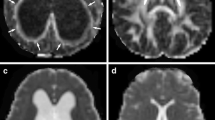

To measure DSI parameters in different white matter regions in patients with iNPH, we used DSI Studio software (http://dsi-studio.labsolver.org/), an accurate traction method, to compute and plot the DSI image data for analysis. The ROIs were drawn manually in the corpus callosum (genu, body, and splenium) of all participants with volumes of 333.8 mm3, 88.6 mm3, and 139.6 mm3, respectively. The ROIs were outlined bilaterally and symmetrically in the right and left internal capsule (IC) (anterior and posterior limb) of all participants with the same size and shape on both sides, with volumes of 40.9 mm3 and 98.8 mm3, respectively (Fig. 2). A neuroradiologist with 15 years of experience delineated all the ROIs. The mean GFA and FA values for each ROI were calculated for statistical analysis.

Seven regions of interests (ROIs) placed along the genu, body, and splenium of the corpus callosum (CC), right and left anterior limb of the internal capsule (IC), and right and left posterior limb of the IC; (A) green, blue, grey, red, pink, and purple indicate the ROIs of the genu of the CC, splenium of the CC, right and left anterior limb of the IC, and right and left posterior limb of the IC, respectively; (B) white indicates the ROI of the body of the CC; (C and D) spatial projection of the seven ROIs on brain regions